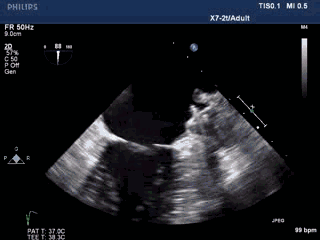

手术过程—全麻下食道超声结合DSA指导房间隔穿刺

穿刺点选择中间略偏后下位。

穿间隔后,给予肝素7000u,测得左房压力12mmHg。